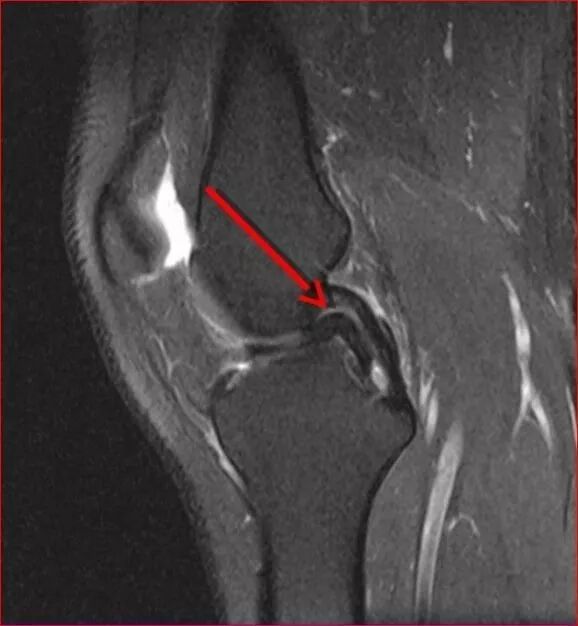

图6 膝关节矢状位 MRI 显示双后交叉韧带征,提示半月板桶柄状撕裂,同时该患者前交叉韧带断裂(未提供图像),手术证实为内侧半月板撕裂所致双后交叉韧带征象

案例一

基本病史:男,62 岁,跌倒后膝关节受伤,负重后疼痛。